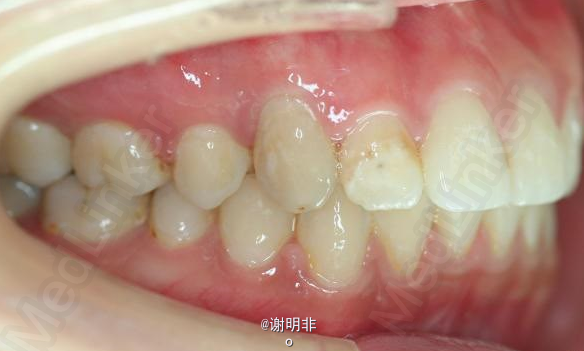

又一例不对称拔牙

牙弓狭窄,牙列拥挤

不对称拔牙